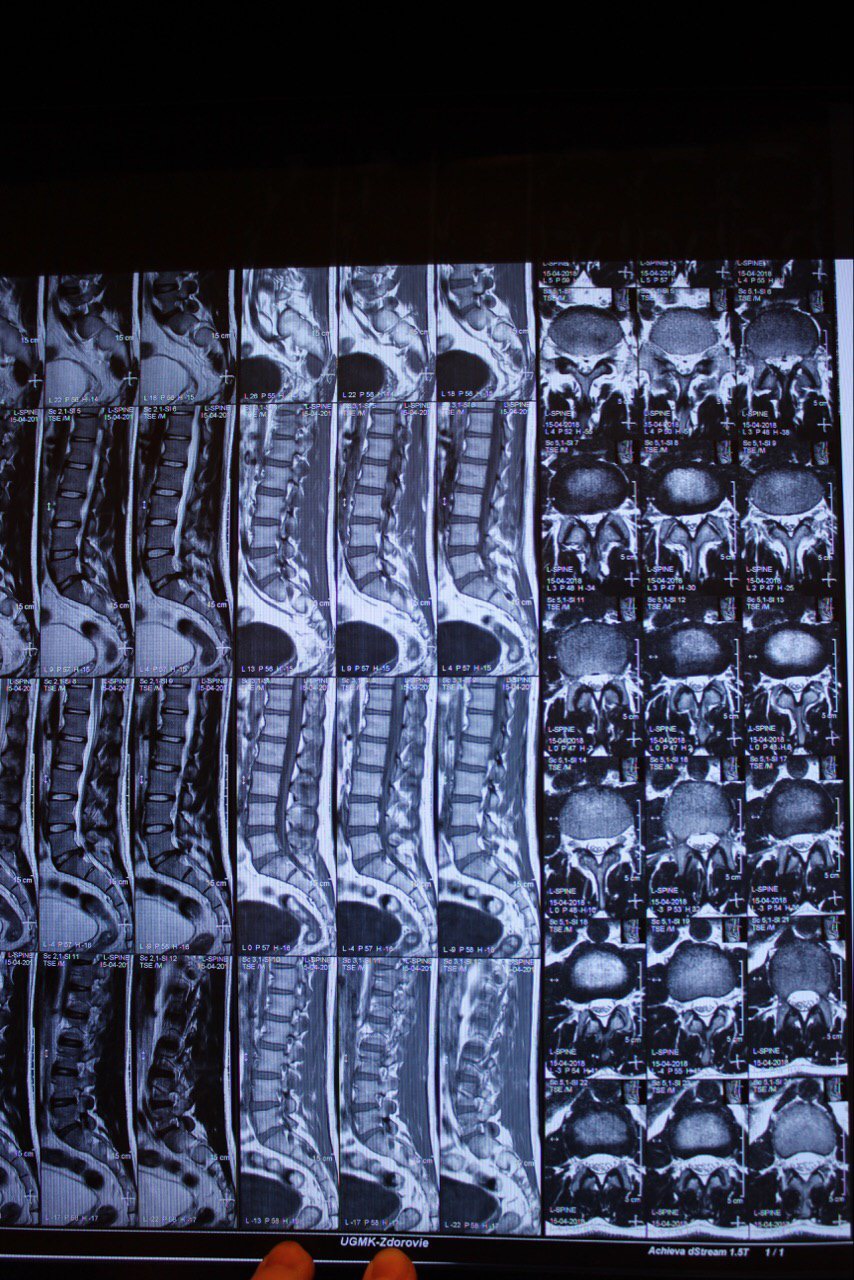

1 это страшное слово "грыжа"